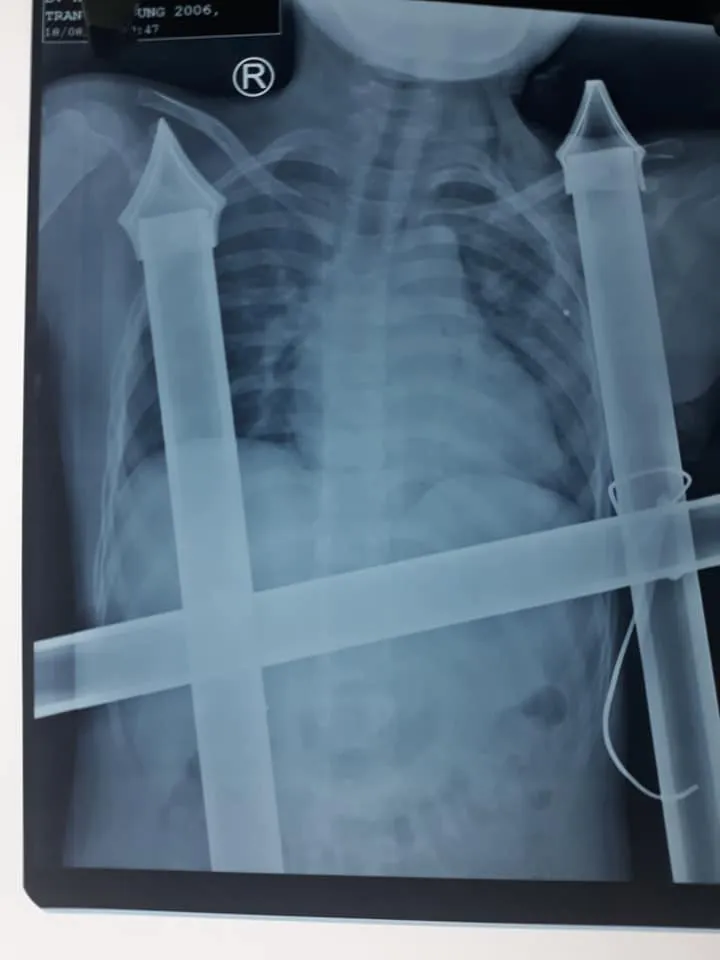

Phát hiện sự việc, mọi người phải dùng cưa sắt cắt một đoạn hàng rào sắt ra mới có thể đưa cháu D. đi cấp cứu. Kết quả chụp X-quang tại bệnh viện xác định, vết đâm của ngạnh sắc nhọn hàng rào đã chạm tới nền sọ của bệnh nhân. Bệnh nhân bị đứt cơ ngực lớn, cọc sắt hàng rào tạo nên đường hầm trong khoang ngực kéo dài trên 10cm.

Bác sĩ Hồ Thái Phúc, Khoa Phẫu thuật Tim mạch lồng ngực, Bệnh viện Hữu Nghị đa khoa Nghệ An cho biết, ê kíp phẫu thuật đã cố gắng tháo đầu sắc nhọn và xử lý tổn thương các mạch máu lớn gây nên tình trạng chảy máu ồ ạt, đe dọa tính mạng của bệnh nhi. Rất may, vật sắc nhọn không làm mạch máu lớn và nội tạng bị tổn thương. Các bác sĩ đã tiến hành rút được dị vật ra khỏi cơ thể bệnh nhân an toàn, đồng thời lau rửa, sát trùng vết thương, khâu cơ ngực…